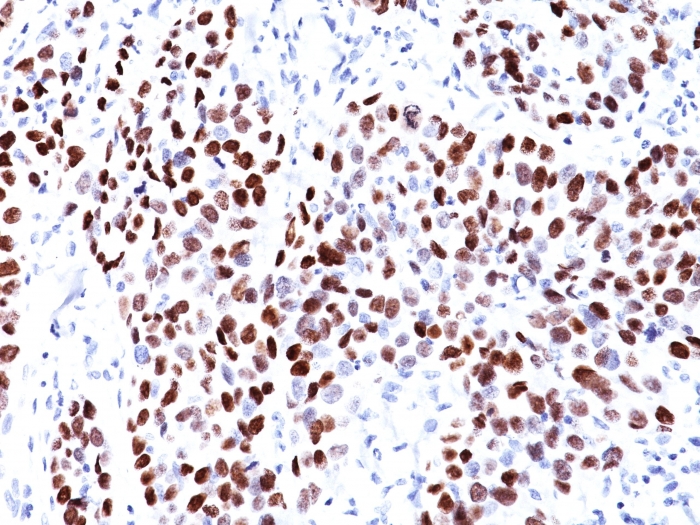

Formalin-fixed, paraffin-embedded human Lung SqCC stained with p21 Mouse Monoclonal Antibody (CIP1/823).

This MAb recognizes a 21kDa protein, identified as the p21WAF1 tumor suppressor protein. This MAb is highly specific to p21 and shows no cross-reaction with other closely related mitotic inhibitors. p21WAF1 is a specific inhibitor of cdk’s and a tumor suppressor involved in the pathogenesis of a variety of malignancies. The expression of this gene acts as an inhibitor of the cell cycle during G1 phase and is tightly controlled by the tumor suppressor protein p53. Its expression is induced by the wild type, but not mutant, p53 suppressor protein. Normal cells generally display a rather intense nuclear p21 expression. Loss of p21 expression has been reported in many carcinomas (gastric carcinoma, non-small cell lung carcinoma, thyroid carcinoma).